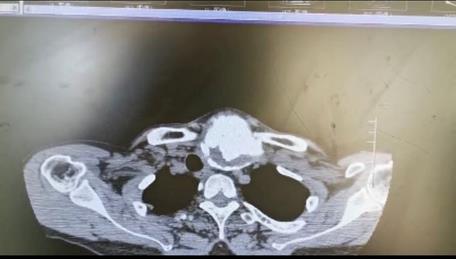

患者朱女士,68歲,頸部包塊呈進行性增大50年,來院后彩超及CT提示左側(cè)甲狀腺腫瘤已經(jīng)超過10公分并邊緣鈣化,氣管移位較明顯,腫瘤較大屬于罕見,不僅給患者造成心理陰影,還影響了正常生活,偶有憋悶不適,進食較大食物感哽咽不適。流動醫(yī)院下鄉(xiāng)義診時,發(fā)現(xiàn)包塊已經(jīng)很大了,影響到頸部的活動及飲食。醫(yī)生與患者及家屬溝通講解病情,表示我們?nèi)揍t(yī)院能治療。最后患者及家屬抱著試一試的態(tài)度來到延安大學咸陽醫(yī)院。

因逐漸長大的頸部嚴重影響飲食及活動,長達50年的折磨,患者身體很瘦、體質(zhì)差。甲狀腺腫瘤,瘤體大,手術創(chuàng)面較大,損傷喉返神經(jīng)及甲狀旁腺風險高,術后可能出現(xiàn)聲音嘶啞及低鈣抽搐等嚴重并發(fā)癥。同時瘤體長期對氣管的壓迫,致術后可能出現(xiàn)氣管軟化而發(fā)生致命性并發(fā)癥。